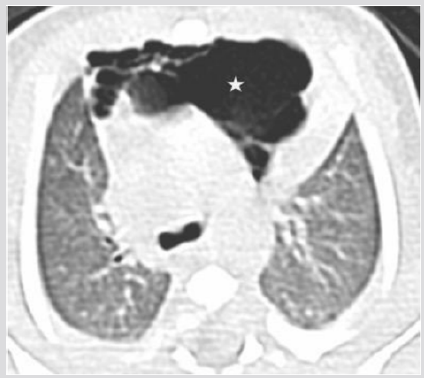

A male was born at 38th week of pregnancy by a regular vaginal delivery; he weighed 2570 g. The prenatal ultrasound follow-up (US) was normal. Mild respiratory distress was noted the first day of life, with occasional expiratory grunting, nasal flaring, and substernal and intercostal retractions. A chestradiography at 24 h of life revealed a left hyper-lucency shifting contralaterally the mediastinum, sharply delineating the left cardiac border and displacing the thymus cranially and laterally (Figure 1). A CT therefore performed revealed a multiloculated gas collection in the anterior mediastinum between the pericardial sac and the left thymic lobe without signs of pulmonary interstitial emphysema (PIE) or pneumothorax (Figure 1). There were numerous thin septa within it. During the second day, the patient was operated for the increasing respiratory distress. A multiloculated air- filled cystic mediastinal lesion was removed. The histopathological pattern demonstrated that the cyst walls were composed of connective tissue. The patient is healed without any complication.

Figure 1B: CT (axial view), Air collection into the anterior mediastinum with multiseptated appearance (star).